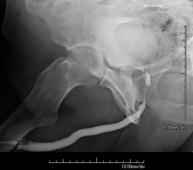

- Hypsterosalpingography (HSG)

Diagnostic test to visualise and study the uterus and fallopian tubes using X-rays and a contrast medium. The patient should be given prophylactic antibiotic treatment. It is recommended that a mild sedative be taken one hour before the test.